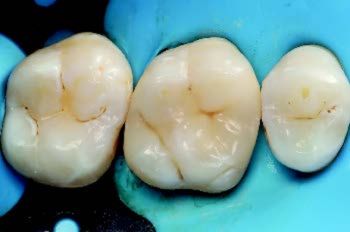

Til slutt ble GC OPTIGLAZE A+ brukt i fissurer for tredimensjonalt utseende (Fig. 4). Etter polering med gummispiralpolerer oppnådde restaureringen høy glans. Kontroll viste korrekt okklusjon uten behov for justering, og pasienten rapporterte ingen postoperativsensitivitet (Fig 5).

Figur 4: Emaljeoppbygging med nøyaktig tilpasning og etterligning av naturlig anatomi samt påføring av overflatetoner (GC OPTIGLAZE A+) i fissurer.

Figur 5: Kontroll av okklusjon og artikulasjonsbevegelser etter fullført restaurering.